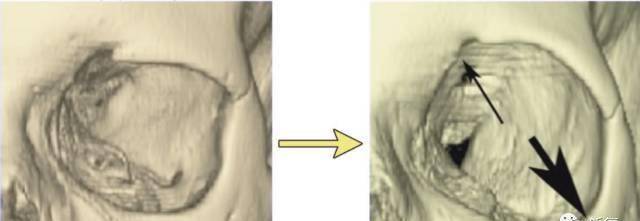

拿眶骨来说 , 图右箭头处是不是出现了明显的骨吸收 , 导致眶骨变大 。

下图可以看出眶骨变化对周围软组织支撑的影响 , 眼袋、泪沟甚至于黑眼圈是不是接踵而来 。

(骨头吸收对软组织的支撑力变小导致的垮)